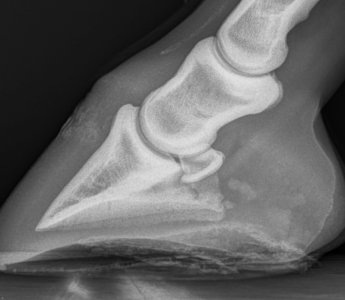

Second photo heel area.

I'm not sure I'd be happy with this area here B. That channel looks like it narrows and also looks like it's forcing the joint apart further back. I'm no expert at xrays though. Ludo and Charlie below for comparison I'm sorry Lari is continuing to cause you worries.

May 23 to March 25, the difference is very clear. Sorry B, even if that isn't the cause of the current lameness you've got a definite issue there. I would personally be particularly worried about how and why the joint is being pushed apart in the middle.

Not from what I can see and from what I see on other x rays of good joints. The joint space shouldn't, I don't think, have got bigger in the middle like that and the culprit looks like arthritis at the front, commonly called low ringbone.